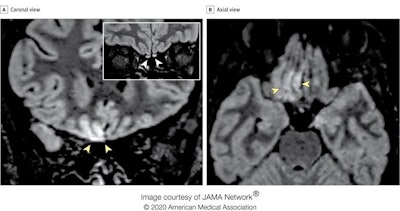

MRI scans of a 25-year-old Italian radiographer who contracted COVID-19 and lost her sense of smell suggest the virus may invade the brain through the olfactory pathway and cause dysfunction of sensorineural origin. This finding was published online by JAMA Neurology on 29 May.

"To our knowledge, this is the first report of in vivo human brain involvement in a patient with COVID-19 showing a signal alteration compatible with viral brain invasion in a cortical region (i.e., posterior gyrus rectus) that is associated with olfaction," noted Dr. Letterio Politi and colleagues from the department of neuroradiology at the Scientific Institute for Research, Hospitalization, and Health Care (IRCCS) Humanitas Research Center, Milan. "Alternative diagnoses (e.g., status epilepticus, posterior reversible encephalopathy syndrome-like alterations, other viral infections, and anti-N-methyl-D-aspartate receptor encephalitis) are unlikely given the clinical context."

The researchers performed two MRI exams on a 1.5-tesla scanner using a 20-channel phased-array head/neck coil. They used no contrast agent and acquired 2D and 3D FLAIR, T2-weighted turbo spin-echo, T1-weighted spin-echo, and high-resolution diffusion-weighted images, Constructive interference in steady-state and susceptibility-weighted imaging sequences were employed.

In follow-up MRI performed 28 days later, the signal alteration in the cortex had completely disappeared and the olfactory bulbs were thinner and slightly less hyperintense. The patient had recovered from anosmia. On 6 May, a blood sample was positive for the immunoglobulin G antibodies against the SARS-CoV-2 virus.